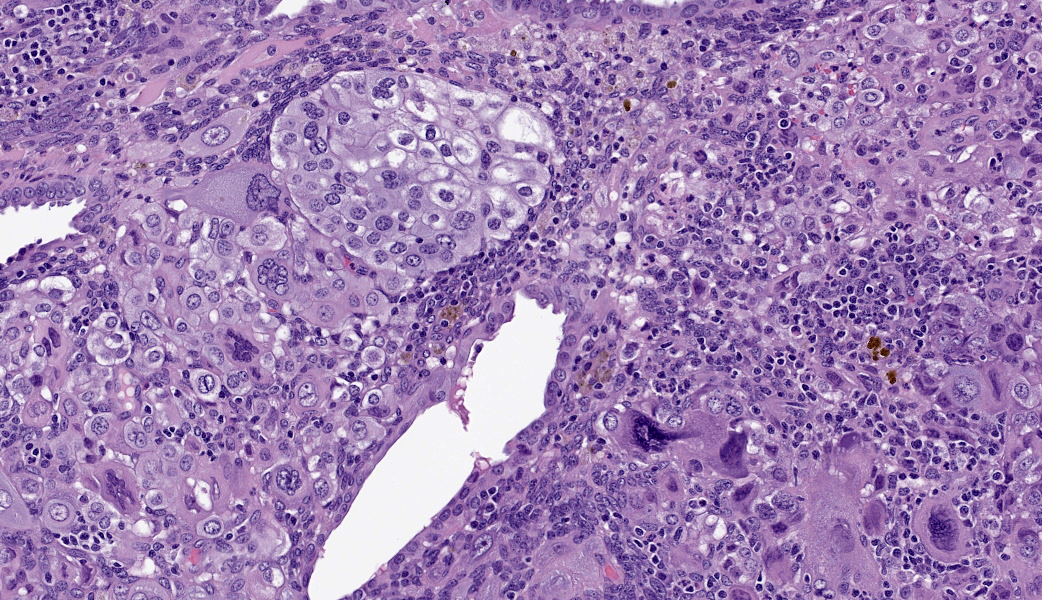

Uterus: Regionally effacing the endometrium, displacing and disrupting the normal glandular and stromal architecture, is a poorly circumscribed, nonencapsulated, infiltrative proliferation of highly pleomorphic round to polygonal neoplastic cells arranged in sheets. The neoplastic proliferation is composed of a biphasic population of uninucleate or multinucleate cells with distinct cell borders, moderate to marked amounts of eosinophilic cytoplasm, and large round vesiculate to finely stippled nuclei and 1-4 variably prominent nucleoli, consistent with a trophoblastic (cytotrophoblasts and syncytiotrophoblasts, respectively) lineage. There are 2 mitotic figures in 10 high power fields (400x). Moderate numbers of lymphocytes and plasma cells are scattered throughout the adjacent endometrial stroma and outer myometrium. Dilated endometrial glands occasionally contain a variable amount of eosinophilic amorphous to basophilic flocculant debris and few macrophages or lymphocytes. Regional erosion of endometrial epithelium is present. The ovary lacks corpora lutea, consistent with sexual immaturity.Slides not provided:

Choriocarcinoma is a neoplasm of trophoblastic lineage that most often arises in women following normal or abnormal pregnancies.1 Diagnostic features include highly pleomorphic, polygonal to round cells with abundant cytoplasm that are both uninucleate (cytotrophoblast or intermediate trophoblast-like) and multinucleate (syncytiotrophoblast) cells, and often a high mitotic rate with metastasis. Morphologic features on histologic evaluation of hematoxylin and eosin-stained uterus from this sexually immature cynomolgus macaque were consistent with choriocarcinoma.In human medicine, choriocarcinoma falls under the umbrella entity of gestational trophoblastic disease. Other neoplasms in this entity include placental site trophoblastic tumor (PSTT) and epithelioid trophoblastic tumor (ETT). PSTTs are composed of a monomorphic population of large, pleomorphic cells derived from implantation-type intermediate trophoblasts. Most cells are uninucleate, but it is not uncommon to see occasional scattered multinucleate cells. ETTs arise from chorionic-type intermediate trophoblasts and present as nests, cords, or solid masses with a monomorphic population of small, round cells.1 Choriocarcinomas tend to have a distinct morphology compared to PSTT and ETT with the presence of uninucleate and multinucleate cells; however, a panel of immunohistochemical markers is commonly used to confirm diagnosis. Characterization with antibodies against hCG, pancytokeratin AE1/AE3, huPL, p63, CD10, PLAPH, and Ki67 provides further support for a diagnosis of choriocarcinoma. These immunohistochemical markers are helpful in distinguishing between PSTT, ETT, and choriocarcinoma (see table).5

Choriocarcinomas are categorized as gestational (associated with pregnancy) or non-gestational (formed in the absence of pregnancy). Some participants were astutely able to deduce from the types of follicles found in the accompanying ovary on the slide that this was very likely a juvenile animal. This, coupled with the lack of gestational change to the uterus, led some to make the jump to a non-gestational choriocarcinoma. Kudos are due to the participants that managed to reason through those subtleties! As mentioned in the contributor’s comment, there are no published examples of primary non-gestational uterine choriocarcinoma in non-human primates.